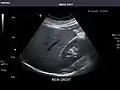

Right kidney